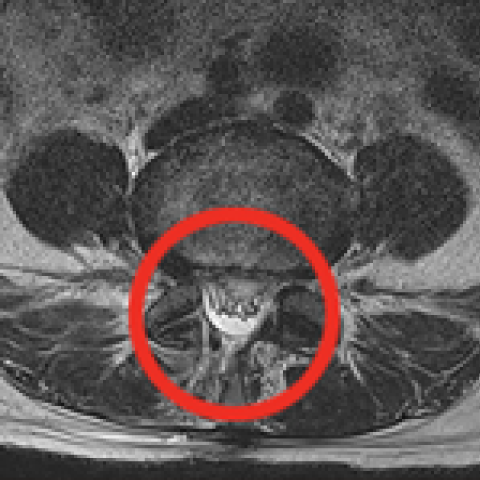

터진 디스크를 내시경으로 제거하는 모습